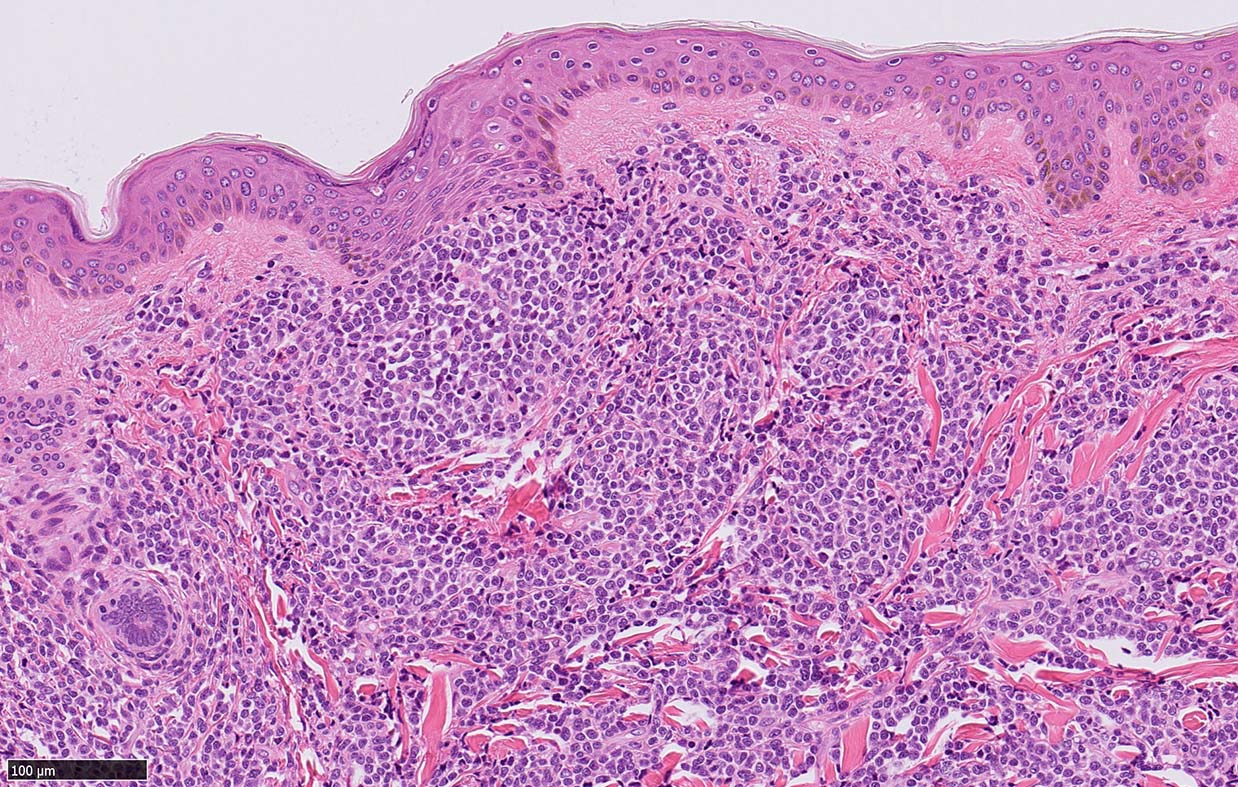

皮膚病変

IWT-case: 4つの点で囲んだ紅斑から生検.

皮膚病変は64-100%の症例で認められ皮膚病変が契機となり診断されることも多い.

マクロ所見は多彩で, 孤在性から播種性の分布を呈し, 腫瘤, 局面, 紅斑いずれの形態もとりえる.

腫瘍細胞は真皮を主座として, 皮下脂肪織まで, びまん性かつ単調monotonousに増殖することが多く, 表皮向性はみられない. 本例では血管や付属器中心あるいは脂肪織内に結節状の浸潤増殖を示した.

本例皮膚真皮増殖細胞はCD4+, CD56+, CD123+, CD303+, lysozyme(-). がん研有明病院, Sakamoto K, Takeuchi K先生にconsultationを行い, TCF4, TCL1の陽性が確認された.(consultationを受けていただいた両先生に深謝いたします.)